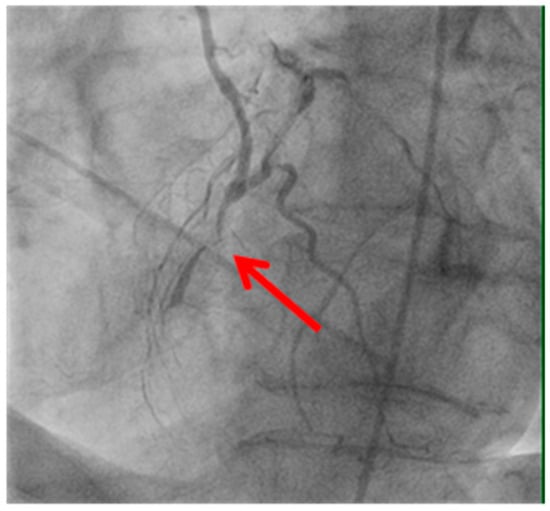

Technical issues remain a principal cause of PMI, with early graft thrombosis or occlusion being leading indications for uCAG (Figure 1, Figure 2, Figure 3 and Figure 4 illustrate typical technical causes, including proximal anastomotic stenosis, kinking, distal anastomotic stenosis, and misplaced anastomoses). Notable contributors include anastomotic stenosis, kinking, overstretching of grafts, and temporary graft spasm [,]. Prueßer et al. demonstrated that 30% of PMI cases detected via CAG were graft-related failures []. In this context, uCAG often reveals technical failures immediately post-surgery, providing the advantage of guiding targeted percutaneous coronary intervention or revascularization. Graft spasm, which can be relieved by nitrates, may also lead to acute ischemia. It refers to the temporary constriction of the bypass graft, reducing blood flow to the myocardium. This condition can be caused by various factors, including surgical trauma, inflammation, or the release of vasoactive substances [].

Figure 4.

Anastomosis performed before the vessel stenosis.

Image illustrating an anastomosis performed before a significant vessel stenosis (shown by the red arrow). Suboptimal graft positioning or incomplete revascularization can contribute to ongoing myocardial ischemia and increase the likelihood of uCAG.